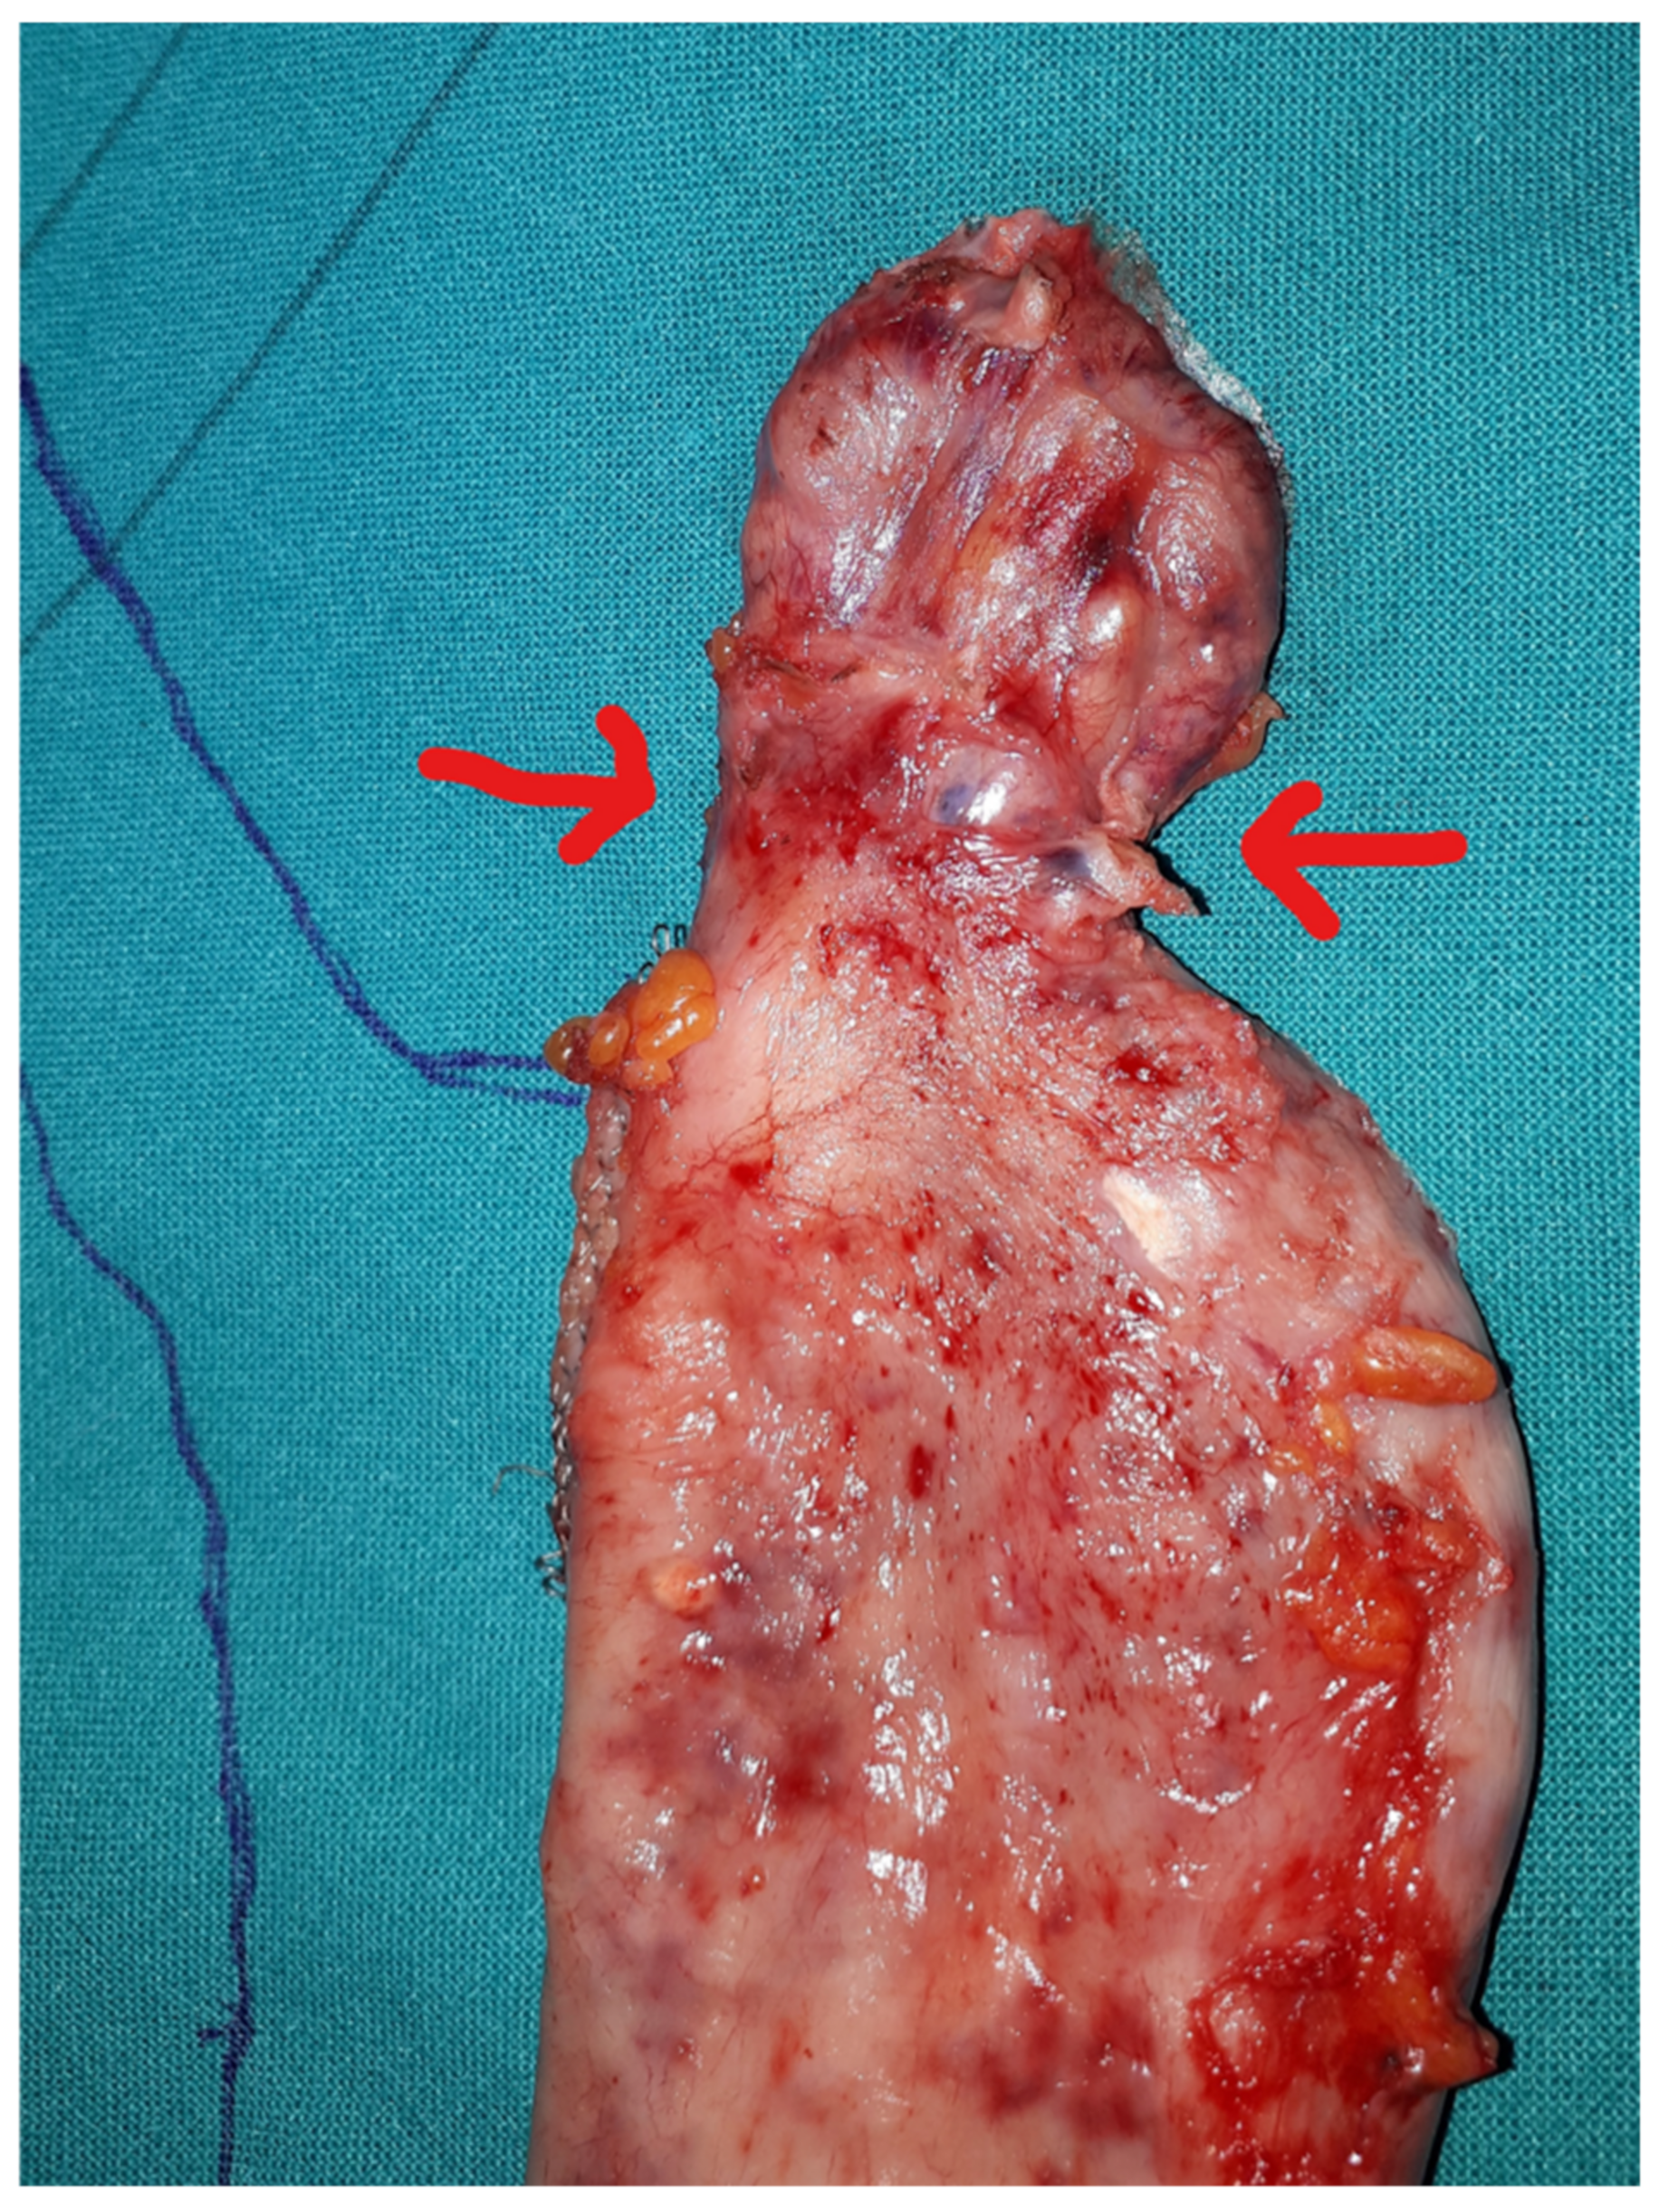

1.2. Technical Considerations

- After the transoral position of a bougie (of diameter ranging 36–40 Fr), sleeve gastrectomy is performed with the use of a stapler, beginning from the distance of 4–6 cm from the pylorus up to the angle of His.

- The staple line should be regular and straight from the antrum to the angle of His.

- The staple line should stay at least 1 cm away from the esophago-gastric junction.